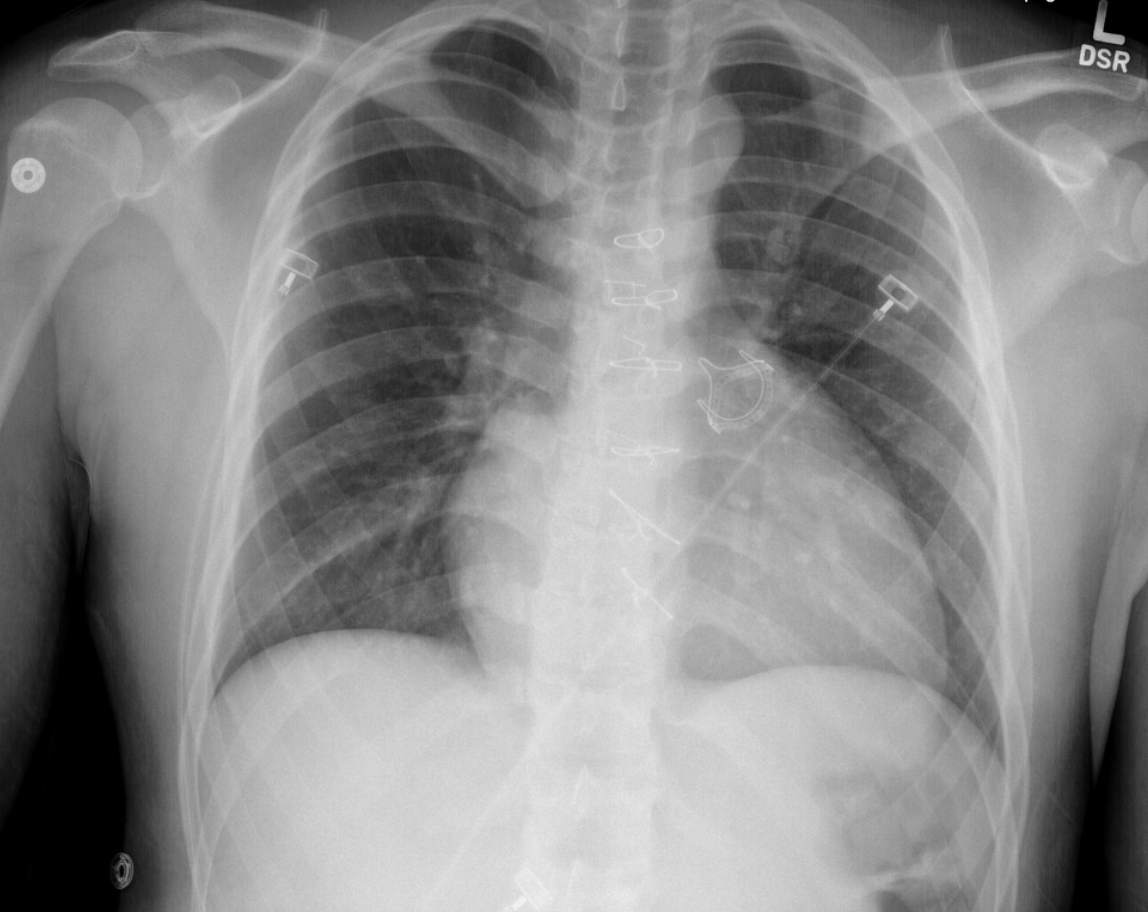

3

Q

A

Atrial lead fracture (right by box), right pleural effusion,